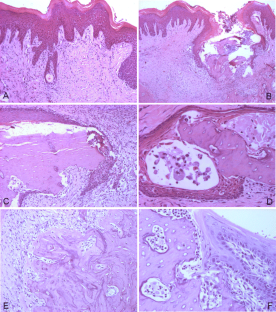

On macroscopic analysis, HBOT did not significantly affect bone exposure volume either at 7 or 14 days. On hematoxylin and eosin (H&E) analysis, the 14-day HBOT group showed less non-vital bone compared to both controls and 7-day HBOT group. HBOT significantly lowered expression of vascular endothelial growth factor (VEGF), receptor activator NF-kB ligand (RANKL), bone morphogenetic protein-2 (BMP-2), and osteoprotegerin (OPG) at 7 days, compared to control, whereas at 14 days, there was no significant difference for these variables.

Fig. 1

Fig. 2